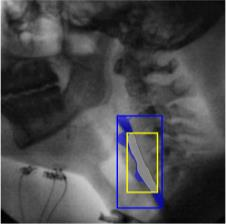

The videofluoroscopic swallowing study (VFSS) is a gold-standard imaging technique for assessing swallowing, but analysis and rating of VFSS recordings is time consuming and requires specialized training and expertise. Researchers have recently demonstrated that it is possible to automatically detect the pharyngeal phase of swallowing and to localize the bolus in VFSS recordings via computer vision, fostering the development of novel techniques for automatic VFSS analysis. However, training of algorithms to perform these tasks requires large amounts of annotated data that are seldom available. We demonstrate that the challenges of pharyngeal phase detection and bolus localization can be solved together using a single approach. We propose a deep-learning framework that jointly tackles pharyngeal phase detection and bolus localization in a weakly-supervised manner, requiring only the initial and final frames of the pharyngeal phase as ground truth annotations for the training. Our approach stems from the observation that bolus presence in the pharynx is the most prominent visual feature upon which to infer whether individual VFSS frames belong to the pharyngeal phase. We conducted extensive experiments with multiple convolutional neural networks (CNNs) on a dataset of 1245 bolus-level clips from 59 healthy subjects. We demonstrated that the pharyngeal phase can be detected with an F1-score higher than 0.9. Moreover, by processing the class activation maps of the CNNs, we were able to localize the bolus with promising results, obtaining correlations with ground truth trajectories higher than 0.9, without any manual annotations of bolus location used for training purposes. Once validated on a larger sample of participants with swallowing disorders, our framework will pave the way for the development of intelligent tools for VFSS analysis to support clinicians in swallowing assessment.